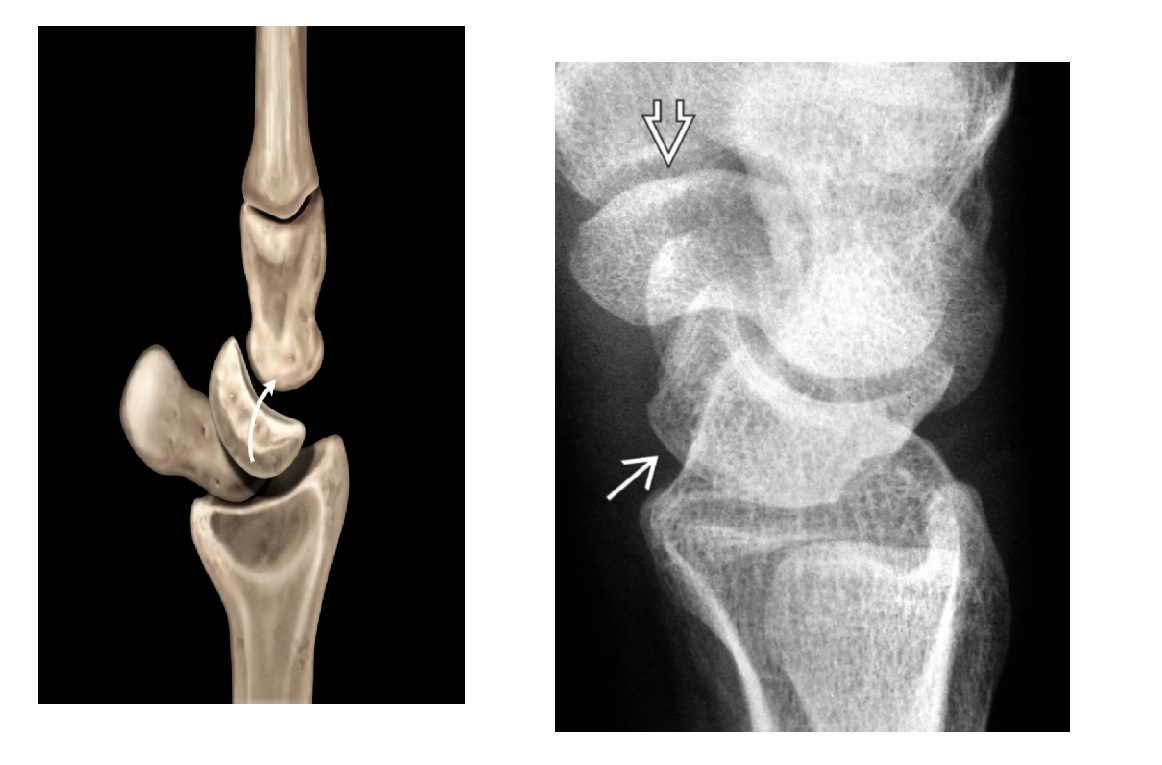

Gamekeepers

Avulsion fracture of the base of the proximal first phalanx

Ulnar collateral ligament disruption

STENER lesion = when adductor tendon gets caught in the torn edges of the UCL = Surgery